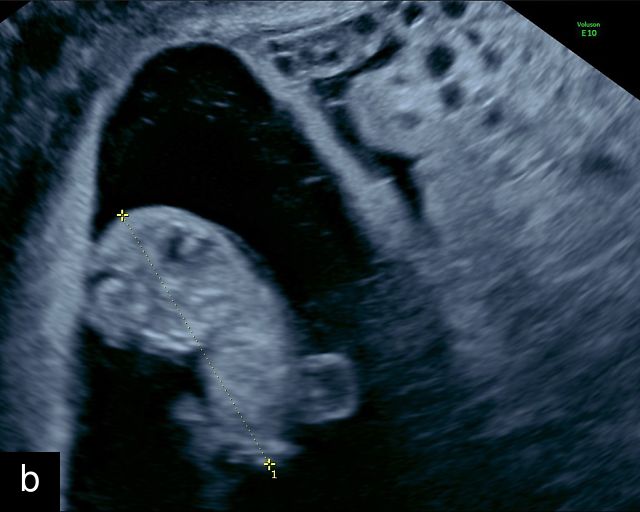

The umbilical cord serves as the lifeline connecting the fetus to the placenta. It arises from the midportion of the fetal abdomen and typically inserts into the center of the placenta (Figure 16). The average length of the umbilical cord is approximately 55 cm (22 inches).185 It contains three vessels: two arteries, which originate from the fetal left and right internal iliac arteries, and one vein, collectively referred to as a three-vessel cord.

16

Normal appearance of the umbilical cord with two umbilical arteries and a single vein. (a–c) Cross-section of the umbilical cord on grayscale (a,b) and power Doppler (c) ultrasound. In the normal cord, three vessels are visible: a larger umbilical vein and two smaller umbilical arteries. This characteristic appearance is often referred to as the 'Mickey Mouse' sign, the larger circle (umbilical vein) representing Mickey’s face while the smaller circles (arteries) form his ears. (d–g) Grayscale (d) and color Doppler (e–g) images of transverse section of the lower fetal abdomen showing the two umbilical arteries diverging around the fetal bladder. (h) Longitudinal ultrasound view with color Doppler of a normal umbilical cord showing three vessels present in each coil: two arteries with flow in one direction and a single vein with flow in the opposite direction.

At a minimum, the mid-trimester ultrasound should include identification and documentation of the umbilical cord's fetal and placental insertions, as well as the number of cord vessels.66,186,187 In a transverse grayscale section of the cord, the two umbilical arteries can be visualized alongside the larger, thinner-walled umbilical vein, creating a characteristic ‘Mickey Mouse’ appearance (Figure 16a–c). Additionally, in a transverse section of the lower fetal abdomen, the umbilical arteries are seen encircling the fetal bladder. This can be seen on grayscale ultrasound and confirmed with color flow Doppler (Figure 16d–g).